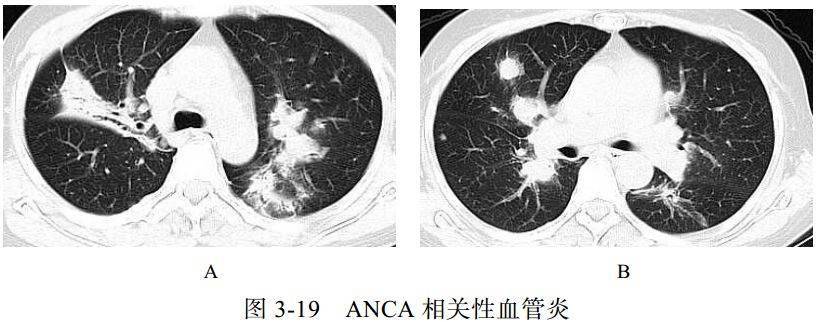

(五)抗中性粒细胞胞质抗体相关性血管炎

抗中性粒细胞胞质抗体(ANCA)相关性血管炎属自身免疫性疾病,是一种坏死性肉芽肿性血管炎。90%的患者伴有鼻窦等上呼吸道病变, ANCA 多呈阳性。该病病变累及小动脉、小静脉及毛细血管,其病理机制以血管壁的炎症为特征。临床表现多样,可累及多系统,如上呼吸道、肺和肾脏发生病变

影像学表现:

(1)多发结节、斑片影(图 3-19),可有充气支气管征及灶性空洞,周围出现磨玻璃样影,常提示肺泡出血或梗死

(2)伴间质性病变,表现为弥漫性网格状影

(3)继发性改变,如支气管扩张或肺结构改变(如蜂窝肺)

(4)非特异性改变,可有胸膜增厚或胸腔积液